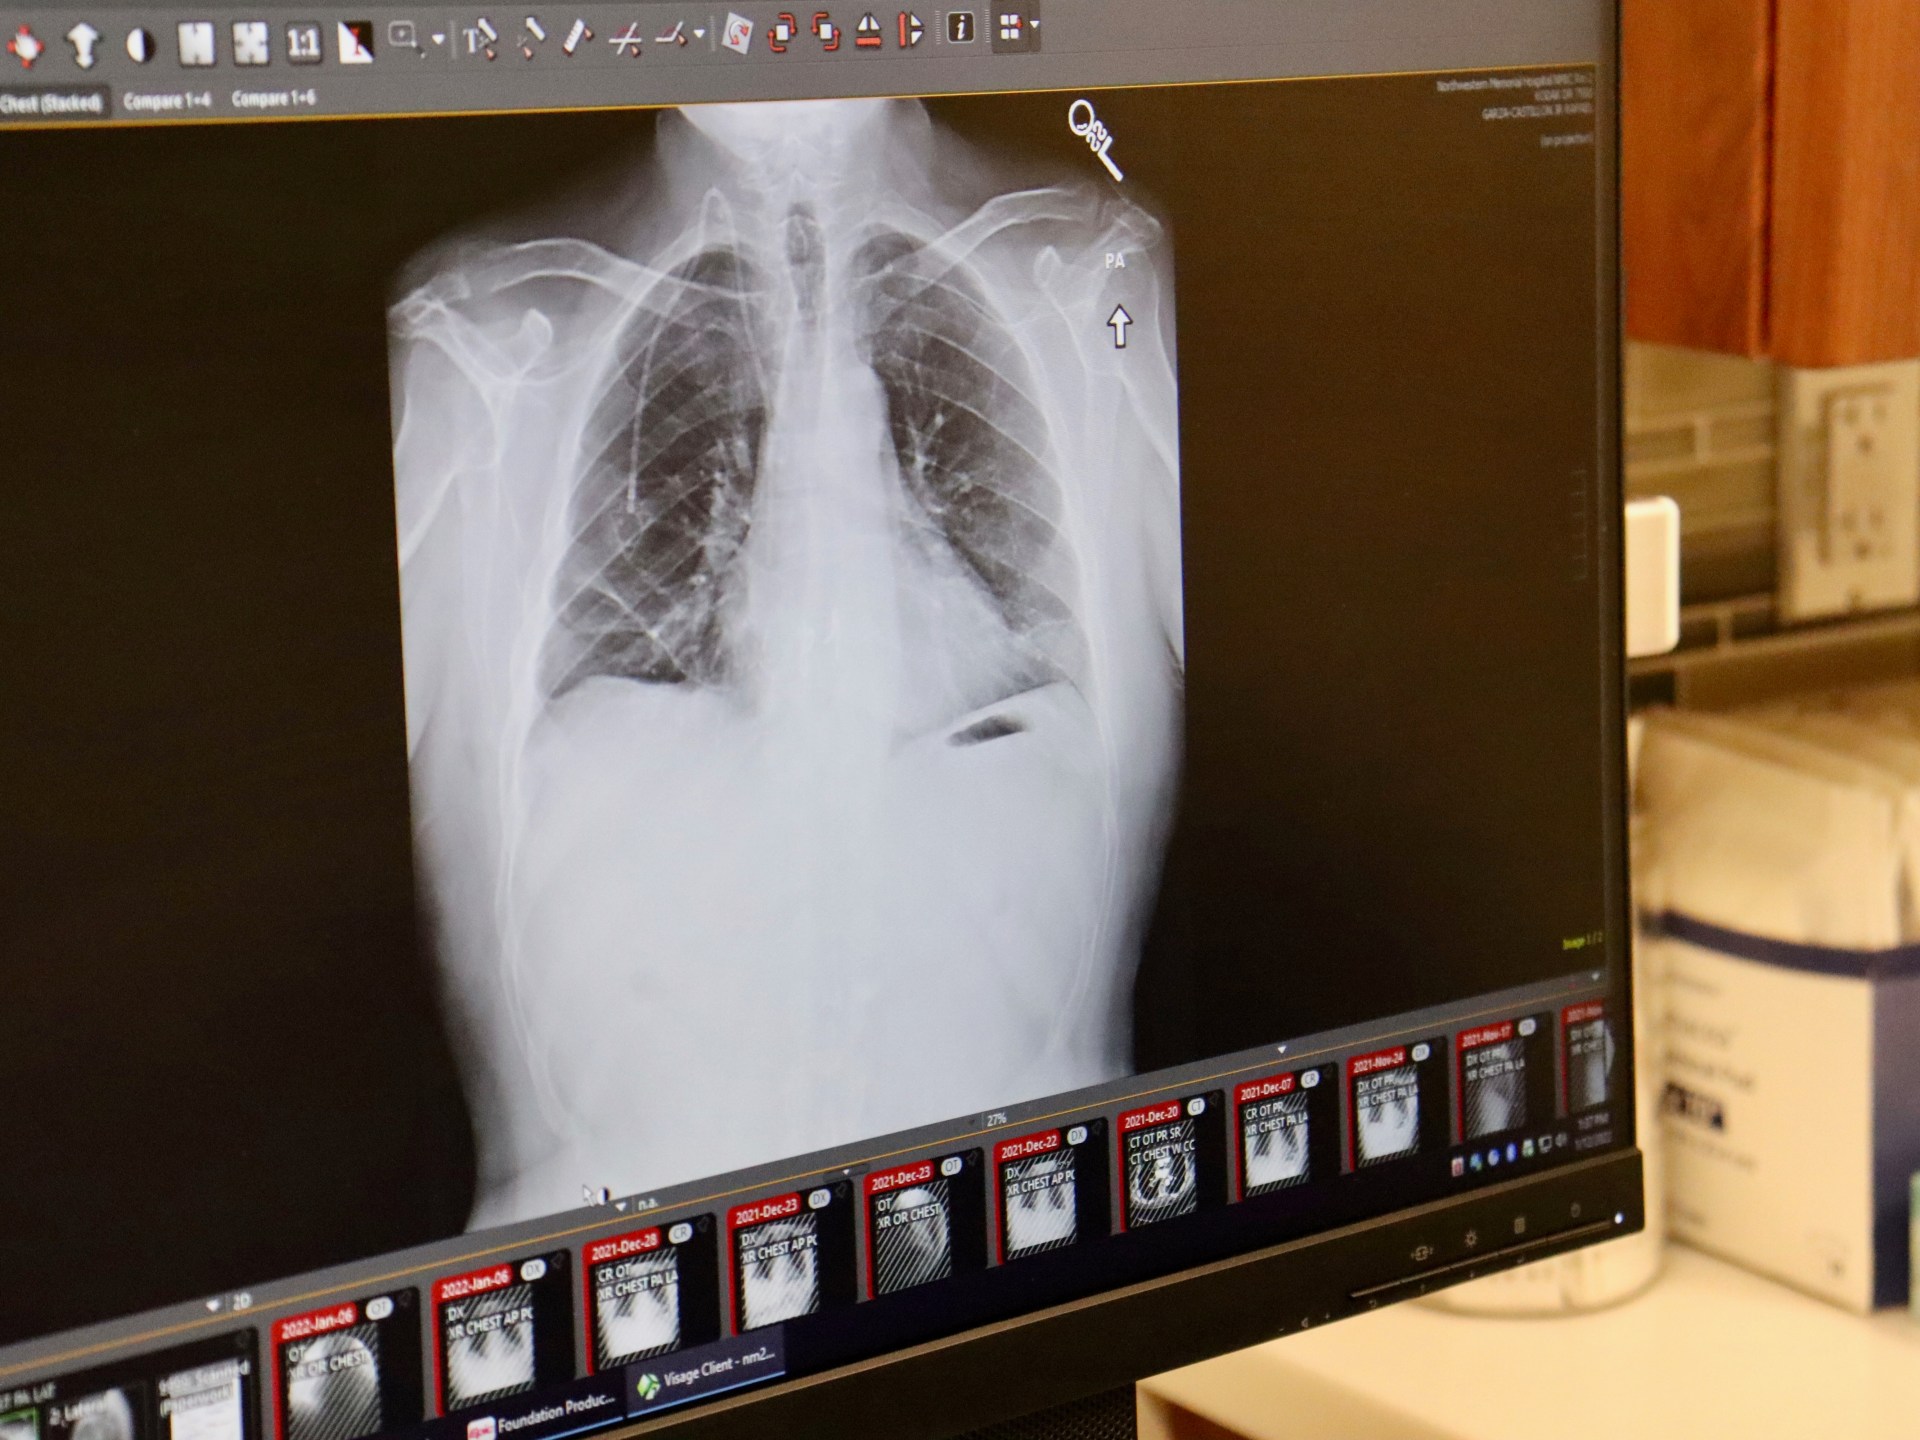

A five-year study published in The New England Journal of Medicine has shown that the lung cancer pill, Osimertinib (Tagrisso), can reduce the risk of recurrent cancer by up to 73% and the risk of death by up to 51% in patients with Stage 1B-3A lung cancer who have a certain genetic mutation and have had surgery to remove cancerous tumors. The results have been described as "earth-shattering" by experts in the field, as the improvement in survival rates far exceeds previous expectations. The pill is part of the growing field of personalized medicine, targeting specific genetic mutations in tumors, and offers hope for lung cancer patients who were previously considered to have a fatal disease.